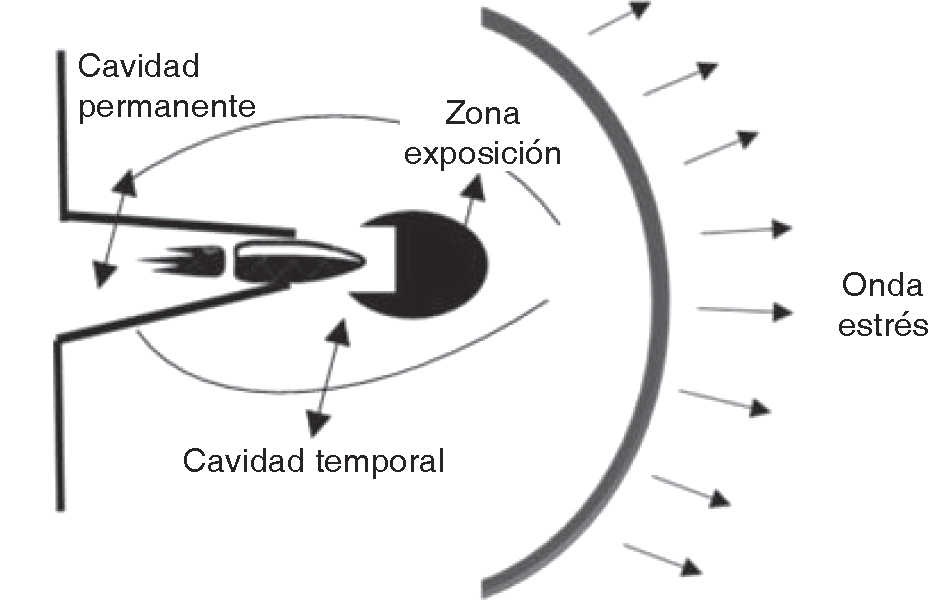

El proyectil de alta velocidad genera una mayor energía cinética comparado con los de baja velocidad, pero asumir que ocasionan un mayor daño es una percepción equivocada. El nivel de injuria va a depender de múltiples factores: energía cinética, capacidad de deformación, fragmentación de la bala y la resistencia a la deformación que presente el tejido alcanzado.5,6 Para nuestra evaluación es de relevancia no sólo la velocidad sino también la zona de impacto, la energía cinética, características de la bala, y el trayecto de penetración para definir el daño, dar un pronóstico y un plan de tratamiento. Al momento de ingresar el proyectil en el organismo crea una cavidad permanente cercana al diámetro del proyectil, una cavidad temporal ocasionada por expansión de la energía cinética de manera lateral, y una onda de estrés hacia delante (Figura 2).2,4 Teniendo en cuenta que la velocidad mínima para perforar la piel es de 50 m/s, y para afectar el hueso 60 m/s.2 La energía cinética que transfiere al organismo produce cambios en la circulación tisular, metabolismo y alteraciones electrolíticas.7 Un factor crítico es la incapacidad del hueso para absorber energía sin fracturarse. Una similitud del hueso y el vidrio en su comportamiento frente a la bala, la distribución de su energía lo convierte en un material frágil.8 Hulkey cols. y ponen en consideración variantes de daño óseo por energía cinética, características de la bala y tipo de tejido: depresión ósea, fractura simple, fracturas conminutas o separación completa de los segmentos óseos. Un proyectil de alta velocidad puede producir fragmentos óseos que salgan en forma de proyectil en dirección de la entrada de la bala. Al contacto con el hueso el proyectil se puede deformar, fragmentar cursando daño mayor al tejido blando.3